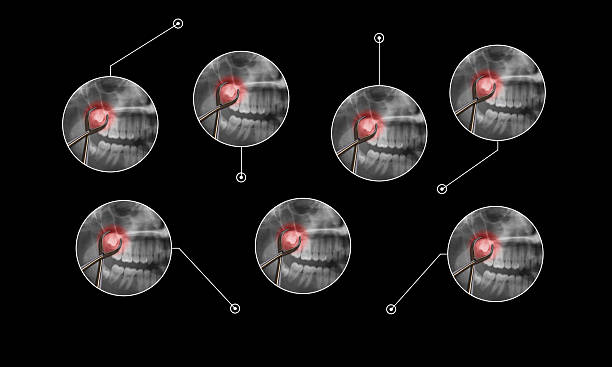

The Wisdom Tooth Removal Procedure

- Initial Consultation : The process begins with a thorough consultation, digital X-rays, and a detailed discussion of your treatment plan.

- Preparation : Local anesthesia or sedation is used to ensure a comfortable, pain-free experience.

- Extraction : The tooth is gently removed, sometimes through a small gum incision. Stitches may be placed if needed.

Why Are Wisdom Teeth Removed?

- Pain and Discomfort : Impacted wisdom teeth can cause severe pain and swelling

- Crowding and Misalignment :Wisdom teeth can push other teeth out of alignment.

- Cyst Formation :In some cases, impacted teeth may develop cysts, damaging surrounding bone and teeth.